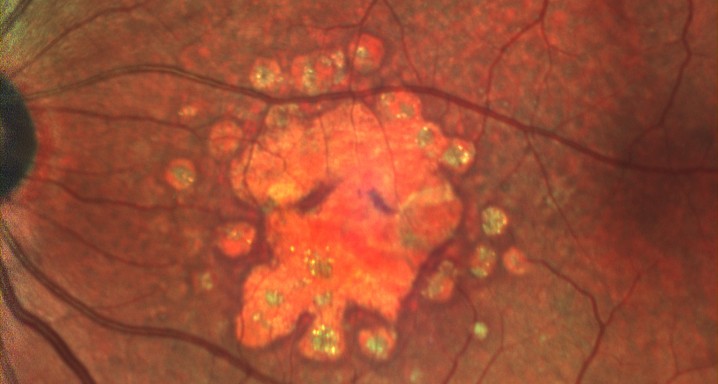

Es un ensayo clínico de fase III, multicéntrico, aleatorizado, con doble enmascaramiento y controlado con tratamiento simulado, para comparar la eficacia y la seguridad del tratamiento con pegcetacoplan por vía intravítrea con inyecciones simuladas en pacientes con atrofia geográfica secundaria a degeneración macular asociada a la edad.

Pacientes de 60 años o mayores que presenten una atrofia geográfica secundaria a la degeneración macular asociada a la edad y que no hayan recibido ningún tratamiento previo en el ojo de estudio.

El tamaño de la lesión deberá estar entre 2.5 y 17.5mm².

Deberá haber hiperautofluorescencia y la visión tendrá que ser igual o mayor a 24 letras (equivalencia Snellen aproximada de 20/320).

El objetivo principal será el de evaluar la eficacia del pegcetacoplan en comparación con la inyección simulada en pacientes con atrofia geográfica secundaria a degeneración macular asociada a la edad, determinada según el cambio del tamaño de la lesión a los 12 meses según autofluorescencia.